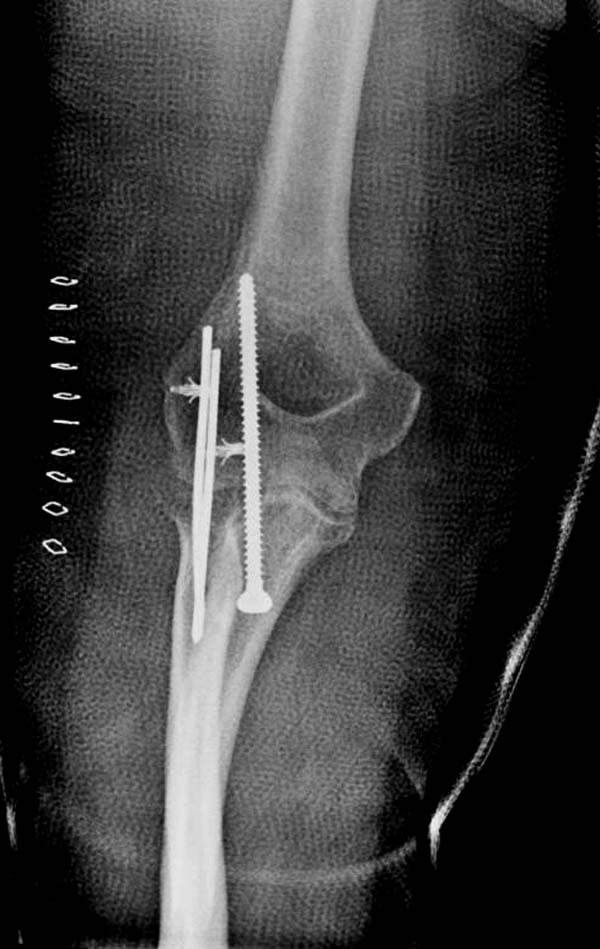

В общем, я хотел сообщить об алгоритме, который применяем у себя. Еще в 1998 году мой партнер по работе Kathy Kramer (скоропостижно скончалась, в ОТА под ее именем имеется грант) написала про наш опыт лечения трансартикулярной фиксацией в 29 случаев вывиха. Кстати, вспомнил прошлогодний спор коллег на Форуме, где площадь повреждения хряща спицами измеряли в мм2. Конечно, такая защита хряща радует, но при игнорированных неделями вывихах? Из-за критики повреждения хряща не позволили опубликовать статью.

Несмотря на отрицательный отзыв, некоторые нестабильные вывихи лечим трансартикулярным методом. Тонкие спицы ломаются и имеют риск внутрисуставной инфекции. Винты 3.5 мм не выдерживают, а более толстые каннюлированные винты неплохо проявили себя. Неосторожность при установке приводила к поломке тонких guide wire внутри сустава. Лучшие кортикальные в 4.5 мм и гипс на три недели. Винт удаляется, затем разработка сустава.

Иногда гипс не гарантировал стабильность и винт внутри гипса ломался. Удаление сломанного винта облегчаем, оставляя на пару мм длиннее с наружной стороны, Т.е винт через олекранон над наружный мыщелок, и никогда в трубку диафиза! Из малого разреза кончик сломанного винта удаляется без проблем.

В заключение: результат применения трансартикулярной фиксации (более 20 лет) в сравнении со сложными реконструктивными операциями показывает лучшую амплитуду движений! Возможно, у коллег имеются другие варианты, а мы без привлечения больших затрат решаем проблему.

Для примера здесь случай начатый в другом центре, а потом переправленный к нам.

Снимки: 1-2 вывих, 4-5 вторичное смещение в гипсе, реконструкция латеральной связки и капсулы 13-14, повторный вывих после реконструкции, перевод в наш центр; 18-21 временная фиксация, 22-25 трансартикулярная фиксация и нестабильная головка фиксирована спицами, 29-30 амбулаторно, 32-33 после удаления винта и спиц...